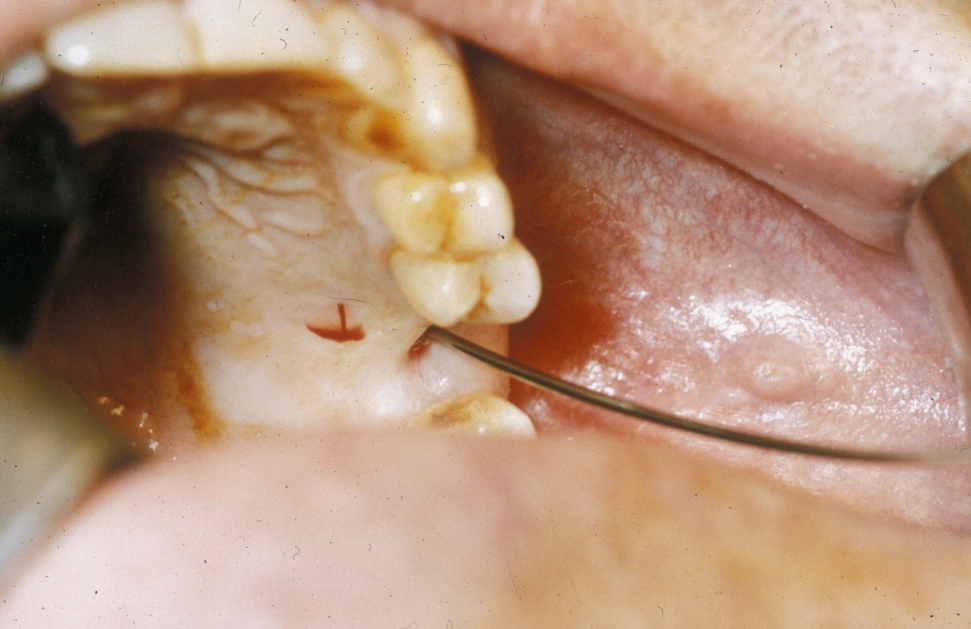

The most common cause for a fistula in the maxillofacial region is a dental abscess, with opening to the mucosa on the inside of the mouth depending on the position of the tooth root. It can rarely open onto the skin (usually from lower front teeth, or a front tooth, onto the chin and may be subjected to multiple ineffective operations by surgeons not aware of the cause). Other common types of fistula are connections between oral and nasal cavity, or connections between the maxillary sinus (hollow space above the upper jaw) and the oral cavity (see Figure 2; this latter type of fistula is a possible complication of tooth extractions in the upper jaw). A cleft palate may be considered a particular type of fistula.

Figure 2: An oroantral fistula, an abnormal communication between the oral cavitiy and the maxillary sinus.